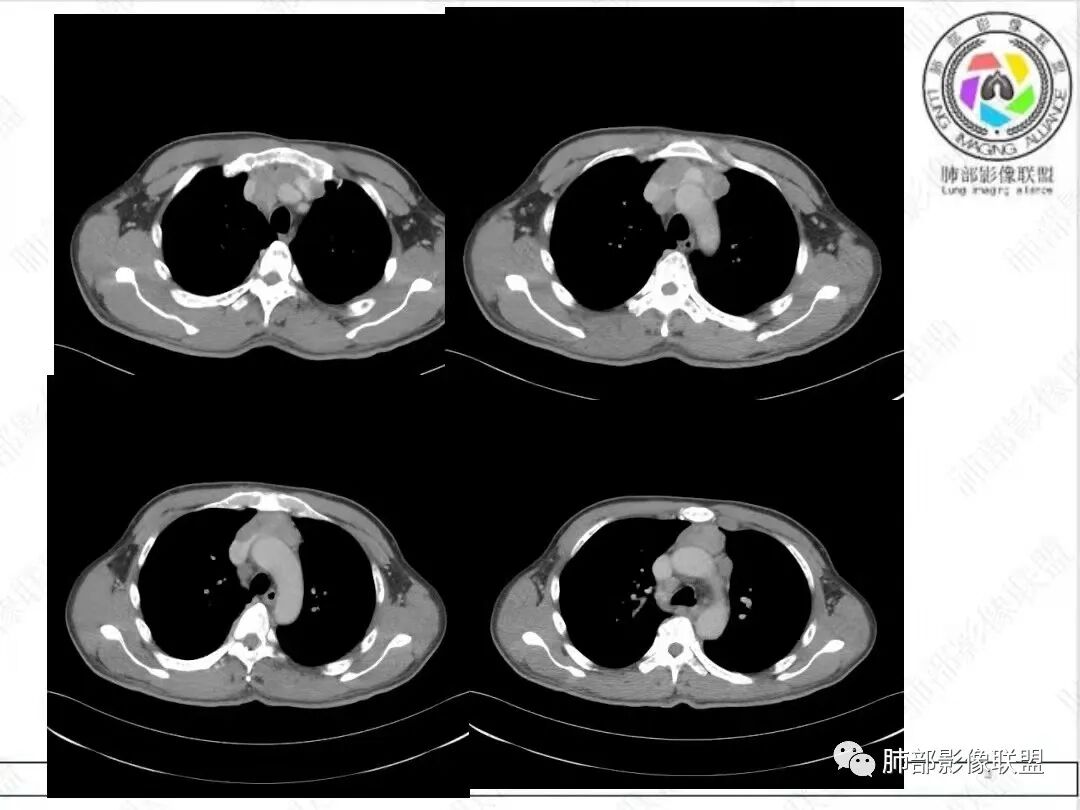

2、影像特点:胸部CT:平扫,前纵隔肿物,基本居中,与周围结构局部分界不清。增强后显示轻中度强化。肿块沿血管间隙侵袭性生长,左无名静脉受压明显变形受侵。纵隔、右肺门多处大小不等淋巴结,左侧内乳淋巴结稍增大。右侧瘤肺交界面光滑,左侧凹陷,肺组织未见明显受侵。右肺中下叶可疑小结节。胸椎及肋骨骨质增生性破坏。肋骨骨折。

病理结果:胸腺不典型类癌。

很多老师提到前纵隔占位+血管肿块内漂浮+内乳淋巴结增大+轻中度强化=淋巴瘤,淋巴瘤确有上述特点,但本例血管漂浮不明确,病灶强化不均匀,胸椎及肋骨可疑增生性转移,应想到胸腺癌或不典型类癌的可能性。